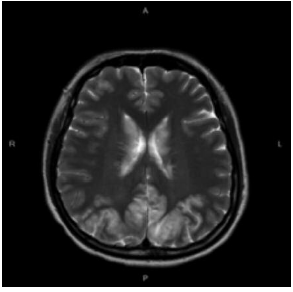

During hospitalization, the patient had persistent hypertension and disturbed vision, with devel-opment of headache. A nonenhanced brain computed tomography showed no intracranial hemorrhage or other significant findings. Therefore, brain magnetic resonance imaging was performed and PRES was diagnosed based on symmetrical lesions in the bilateral occipital lobes (Figure 1). Antihypertensive agents for aggressive blood pressure management and hydrocortisone for improving vasogenic edema were administered. With her hemodynamic con-dition relatively stable, the patient received emergent LDLT.

Four days after transplant, the patient had a seizure attack with loss of consciousness. Repeated brain magnetic resonance imaging scans showed diffuse swelling of cerebrum and cerebellum with uncal herniation and brainstem compression, so PRES progression was highly suspected. With thorough surveys of triggers, besides liver transplant, tacrolimus intoxication (therapeutic drug level of 21.4 ng/mL) was thought to be the primary cause to worsen PRES. Because of this, tacrolimus was promptly suspended. After the abrupt episode, rapid impairment of liver function, hyperbilirubinemia, thrombocytopenia, and prolonged prothrombin time/activated partial thromboplastin time occurred. Doppler sonography showed reduced flow of grafted intrahepatic vessels without thrombotic formation of anastomotic sites (Figure 2). An emergent computed tomography with contrast of abdomen showed hypo- and nonen-hancement (Figure 3), and gross hepatic infarction was diagnosed. The patient gradually deteriorated with sequential multiple organ failure and died 7 days after LDLT.